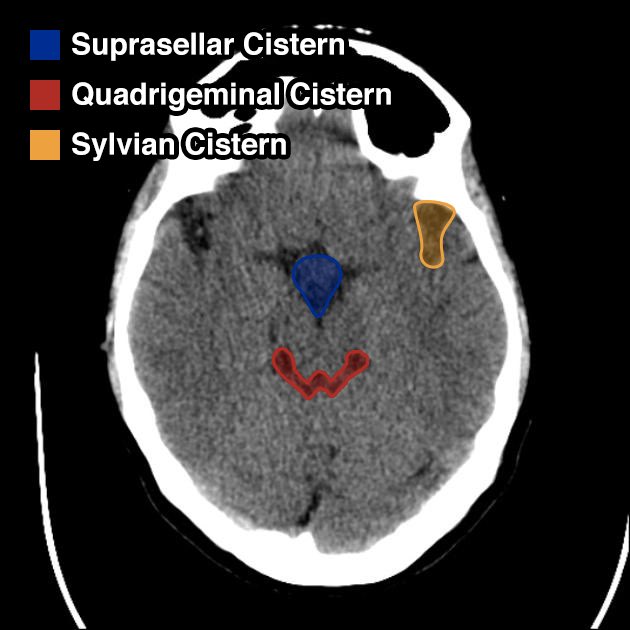

▫️الحرف الثاني هو ال “C”

⬅️ويقصد فيه⬅️ Cisterns

✳️تمثل مساحات مليئة بالسائل الدماغي الشوكي "CSF” وكونها متصلة يعتبر شيء أساسي لل CSF circulation

✳️Related pathology✳️

Mass effect and ⬆️ ICP ➡️ effacing one or more of the cisterns

Subarachnoid hemorrhage

arachnoid cyst